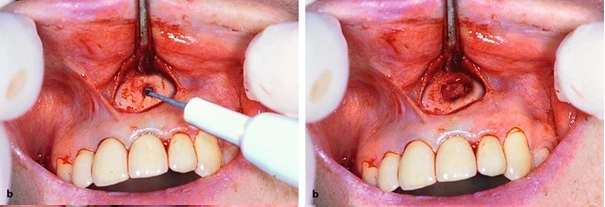

Tay khoan thẳng với mũi tròn có rãnh xoắn lớn mở cửa sổ xương tiếp cận vùng chóp

Xoang trám đã được tạo xong. Bây giờ thì nhồi vật liệu trám vào thôi, ngày nay người ta chuộng MTA cho những công việc này hơn là Almagam vì những ưu điểm vượt trội của nó (xin được trình bày vào một dịp khác)